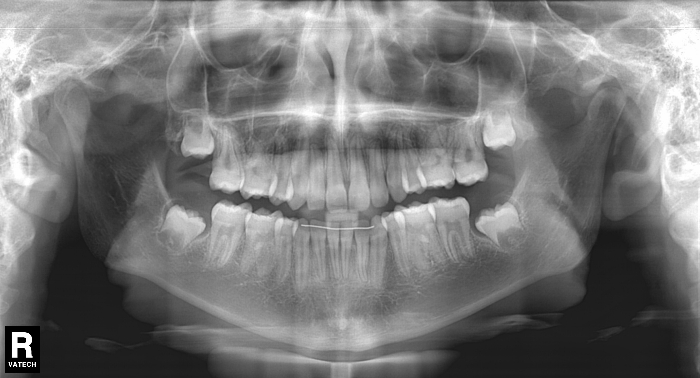

La paciente O.O. acude a nuestra consulta por:

– Canino 13 e incisivo lateral 42 en posición ectópica.

– Canino 23 incluido.

Con lo que decide realizarse un tratamiento de ortodoncia de duración de 24 meses con brackets damon Q.

CASO COMPLETO: